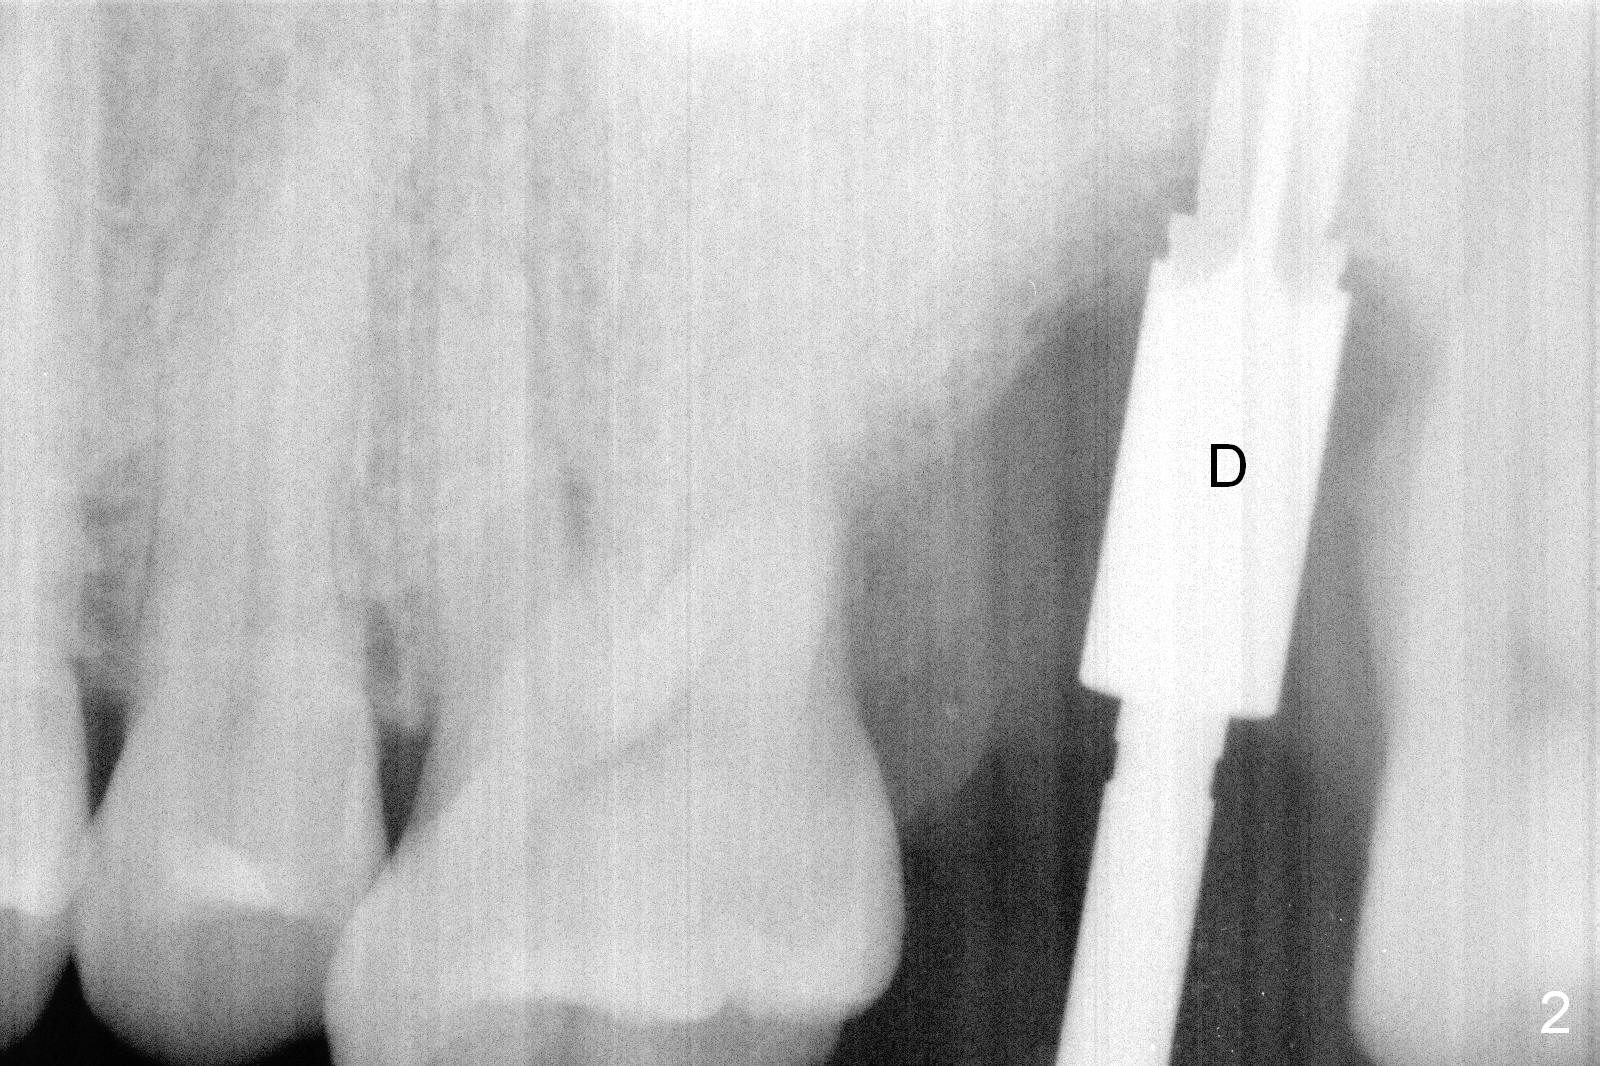

When the tooth #15 is extracted, the buccal plate is found to have been lost. The depth of osteotomy in the native bone is 8.5 mm (Fig.1,2). When a 5.5x15 mm implant is placed (Fig.3), the insertion torque is > 55 Ncm. The implant is palatally placed with a 10x10 mm Osteogen plug being placed in the deep portion of the buccal gap for buccal plate repair (Fig.4 *). The superficial portion of the remaining socket is filled with .5-1.5 mm allograft/autogenous bone/Osteogen (Fig.5 *). The drawback of this procedure is that the abutment is placed prior to placement of the graft. The latter fails to reach the deepest area of the defect. If periimplantitis develops because of insufficient graft, do it again in due time.